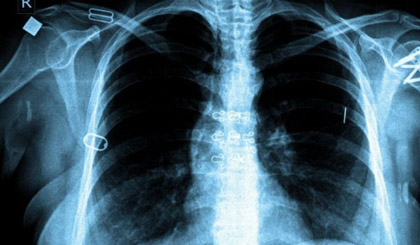

| Ảnh: BBC. |